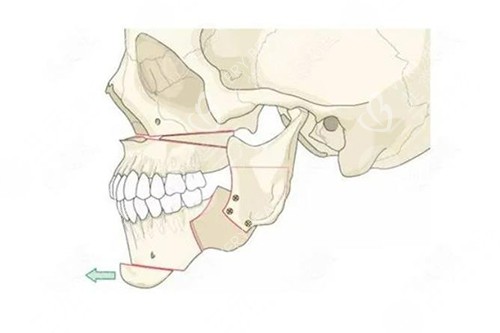

牵张成骨术,是一种内源性骨组织工程技术,通过外科手段将骨骼切开,在切骨线两侧安装特制的牵张器,经过一定的延迟期后,缓慢牵张切骨间隙,使间隙不断增宽,并激发机体组织再生的潜力,在牵张间隙内不断形成新生骨组织。同时,该技术还能使骨骼周围的肌肉、神经、血管、皮肤等软组织同期延长,从而达到延长骨骼、改善形态的目的。

颅面畸形矫正:如小下颌畸形(mandibular micrognathia)、半侧颜面发育不全综合症(hemifacial microsomia)以及各种颅面畸形综合症,如Nager syndrome、Pierre-Robin syndrome、Crouzon syndrome、Treacher-Collins syndrome、Craniofacial synostosis等。